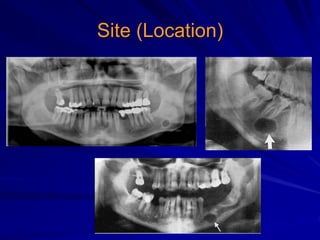

Site (Location)

Localized

Generalized

Multiple

Unilateral

Bilateral